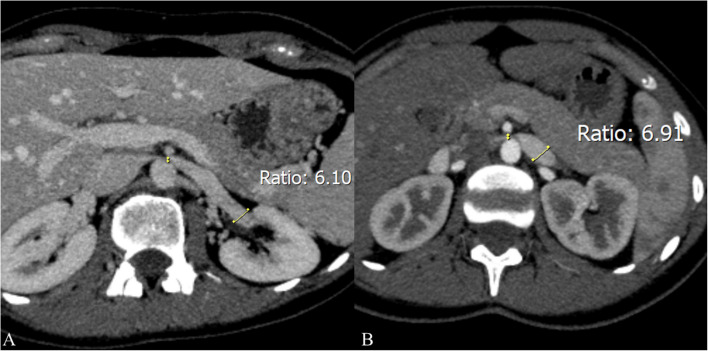

胡桃夹子综合征(NCS)是一种相对罕见的血管疾病,其特征是左肾静脉(LRV)受压,导致多种非特异性症状,包括血尿、侧腹疼痛、精索静脉曲张和盆腔充血综合征。LRV受压来源可分为前、后两种:前路NCS发生于LRV受压于主动脉与肠系膜上动脉之间,后路NCS发生于主动脉与脊柱之间。尽管诊断方式有了进步,包括多普勒超声、计算机断层扫描、磁共振成像和侵入性技术,如静脉造影术,但仍然没有全球公认的诊断算法,导致诊断不一致。此外,由于缺乏标准化的治疗指南,前路NCS的最佳治疗仍然是一个有争议的话题。虽然在儿童人群中通常推荐保守治疗,但侵入性治疗——包括LRV转位和肾脏自体移植等手术选择,以及介入放射治疗(如支架置入术)——存在支架移位、再狭窄和材料长期耐用性等挑战。尽管如此,3d打印支架的出现为患者特异性治疗提供了潜在的改进,特别是在儿科人群中,但其临床疗效和安全性仍在调查中。本文简要介绍了目前关于前路NCS治疗的讨论,强调需要标准化的诊断算法、多学科方法和持续的技术进步来完善治疗可能性和策略。进一步的研究对于解决这些争议和就最佳做法达成共识至关重要。

Nutcracker syndrome (NCS) is a relatively uncommon vascular condition characterized by compression of the left renal vein (LRV), resulting in a variable spectrum of nonspecific symptoms, including hematuria, flank pain, varicocele, and pelvic congestion syndrome. NCS can be classified into anterior and posterior types regarding the origin of LRV compression: anterior NCS occurs when LRV is compressed between the aorta and superior mesenteric artery, whereas posterior NCS involves LRV compression between the aorta and the spine. Despite advancements in diagnostic modalities, including Doppler ultrasound, computed tomography, magnetic resonance imaging, and invasive techniques like phlebography, there is still no globally accepted diagnostic algorithm, leading to inconsistencies in diagnosis. Moreover, due to the lack of standardized treatment guidelines, the optimal management of anterior NCS remains a topic of debate. While conservative management is usually recommended in the pediatric population, invasive treatments-including surgical options like LRV transposition and renal autotransplantation, as well as interventional radiology procedures like stenting, present challenges such as stent migration, restenosis, and long-term material durability. Nevertheless, the emergence of 3D-printed stents offers potential improvements in patient-specific treatment, particularly in the pediatric population, yet their clinical efficacy and safety remain under investigation. This brief communication addresses the current discussions regarding anterior NCS management, emphasizing the need for standardized diagnostic algorithms, a multidisciplinary approach, and continued technological advancements to refine treatment possibilities and strategies. Further research is critical to resolve these controversies and establish a consensus on best practices.